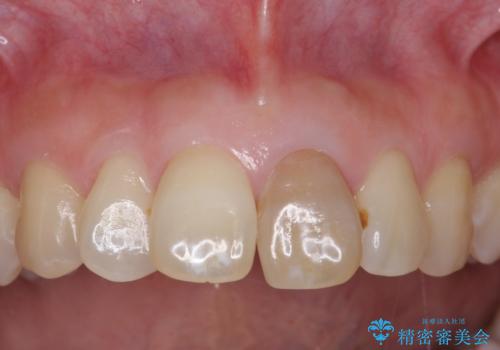

- 前歯のブリッジのやり替えをご希望されました。

かみ合わせが強く、以前入っていた保険治療のブリッジも前装が欠けてしまっていました。

セラミックも強い衝撃で欠けないわけではないため、強度のあるフルジルコニアクラウンでブリッジを作成しました。

フルジルコニアクラウンはやや白すぎるといった難点がありますが、今回は強度を優先することにしました。